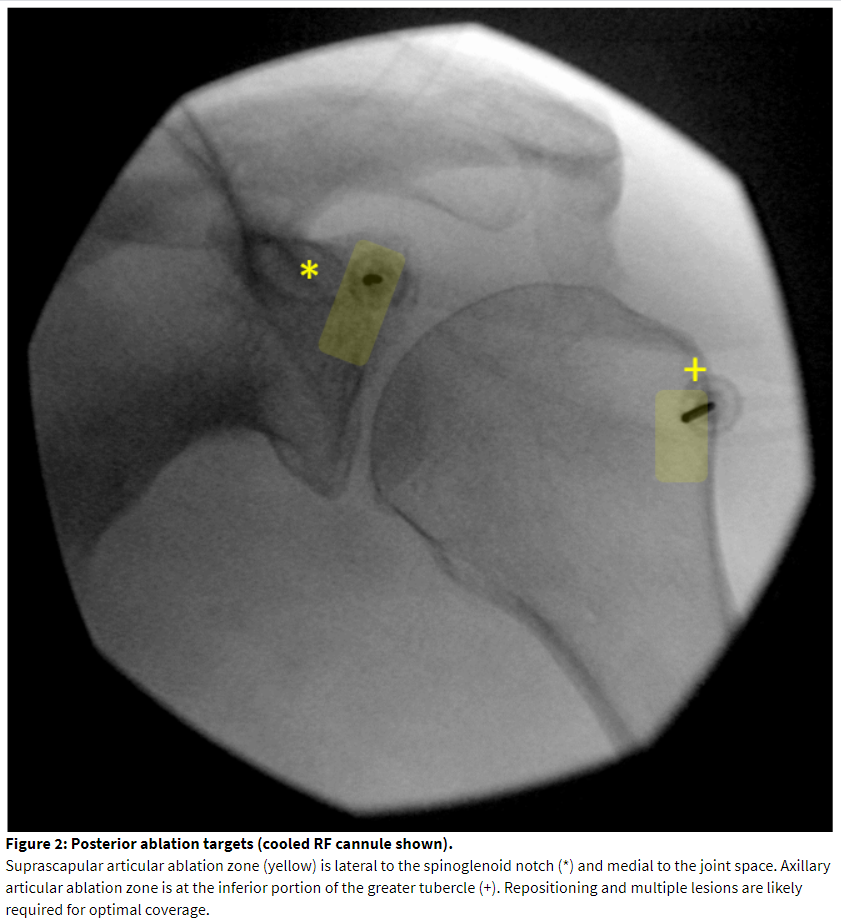

Diagnostic Block Technique: Supine Approach

Supine positioning provides access to the lateral pectoral nerve and the nerve to subscapularis. An annotated image, needle placement, and ablation zone is illustrated in Figure 3. The patient is positioned with the operative arm at the side. The coracoid process should be visualized. In the neutral anteroposterior view, it will appear as a circle or oval image. Cephalad and ipsilateral rotation will elucidate better contour of the superficial surface of the coracoid process. This also will show the joint line and the neck of the glenoid. The superficial midpoint of the coracoid process is a recommended target for lateral pectoral block and ablation[29] and is often 2-3 cm below the skin surface. Placing the needle in the superior-anterior-lateral aspect of the neck of the glenoid will block the articular branch from the nerve to subscapularis.[27] This is approximately 1-1.5 cm deeper than the coracoid target. If both posterior and anterior targets are needed for the case, care must be taken to carefully assist the patient in flipping.

Lateral pectoral nerve ablation is performed over the mid-portion of the coracoid process from an anterior approach (Figure 3). This location is superficial. If the depth of the cannula tip is less than 1.5 cm, consider alternate methods for ablation such as chemical neurolysis in order to reduce the risk of skin injury. Placing a standard RF cannula in a medial to lateral and caudal to cranial direction matches the path of the nerve.[28] Ultrasound can be as a sole imaging modality. The accompanying branch of the thoracoacromial artery serves as a landmark for needle placement. If ultrasound is not used, we recommend placing a small gauge “finder” needle to exclude vascular return and protect against vascular trauma with a large bore RF cannula. Pectoral muscle stimulation should be excluded but is rarely encountered. If pectoral muscle contraction is encountered, the needle tip should be redirected laterally on the coracoid process. Contraction of the upper extremity should alert the practitioner to inadvertent positioning of the needle deep to the coracoid process and close to the brachial plexus.

Ablation of the nerve to subscapularis is undergoing preclinical and clinical investigation at the time of this publication. The authors have blocked the articular branch with success. The target can be seen in the same fluoroscopic view as the lateral pectoral block as described above. The needle tip should contact the upper lateral aspect of the anterior glenoid neck, traversing cranially to the coracoid process, from an anterior approach. The needle tip should remain medial to the joint line to avoid injury to the labrum and attachment of the biceps tendon. The needle tip should not be caudad to the coracoid process because this can endanger the brachial plexus and axillary artery. For this reason, the coracoid process is referred to as the “Lighthouse of the Shoulder.”